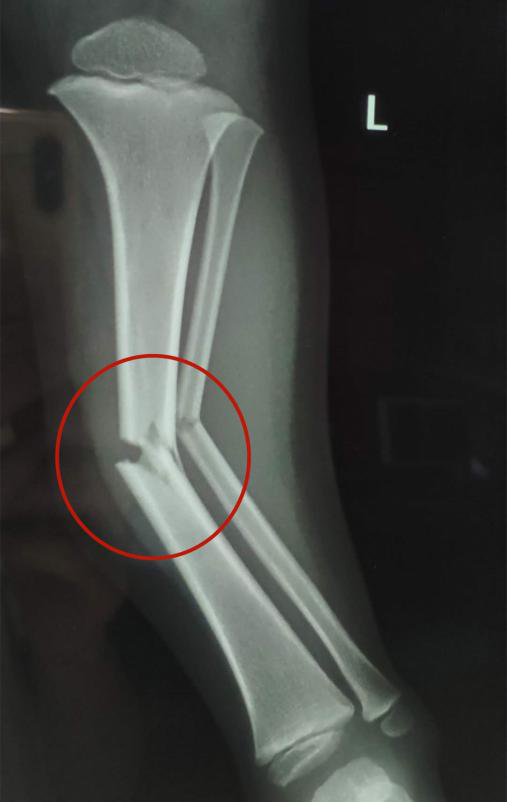

接診的瀘州市中醫(yī)醫(yī)院骨傷一科副主任中醫(yī)師李孟澤查看了患兒之前的X光片及左下肢情況,發(fā)現(xiàn)其骨折移位較大(骨折處彎曲呈30度角以上),導致左下肢中段嚴重畸形。

手法復位前X片顯示脛腓骨斷端,左下肢中段嚴重畸形